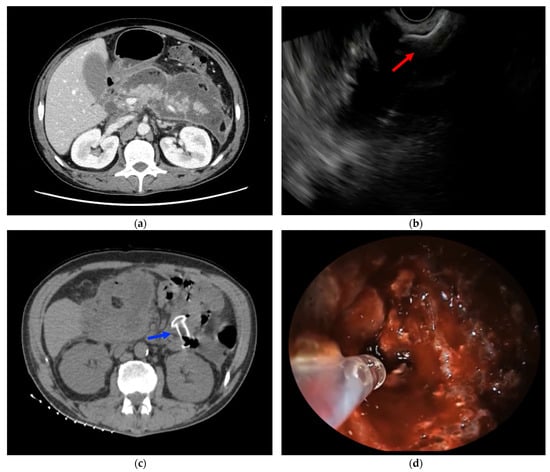

3.2. Procedure Details

3.3. Bleeding Management and Prevention with PuraStat